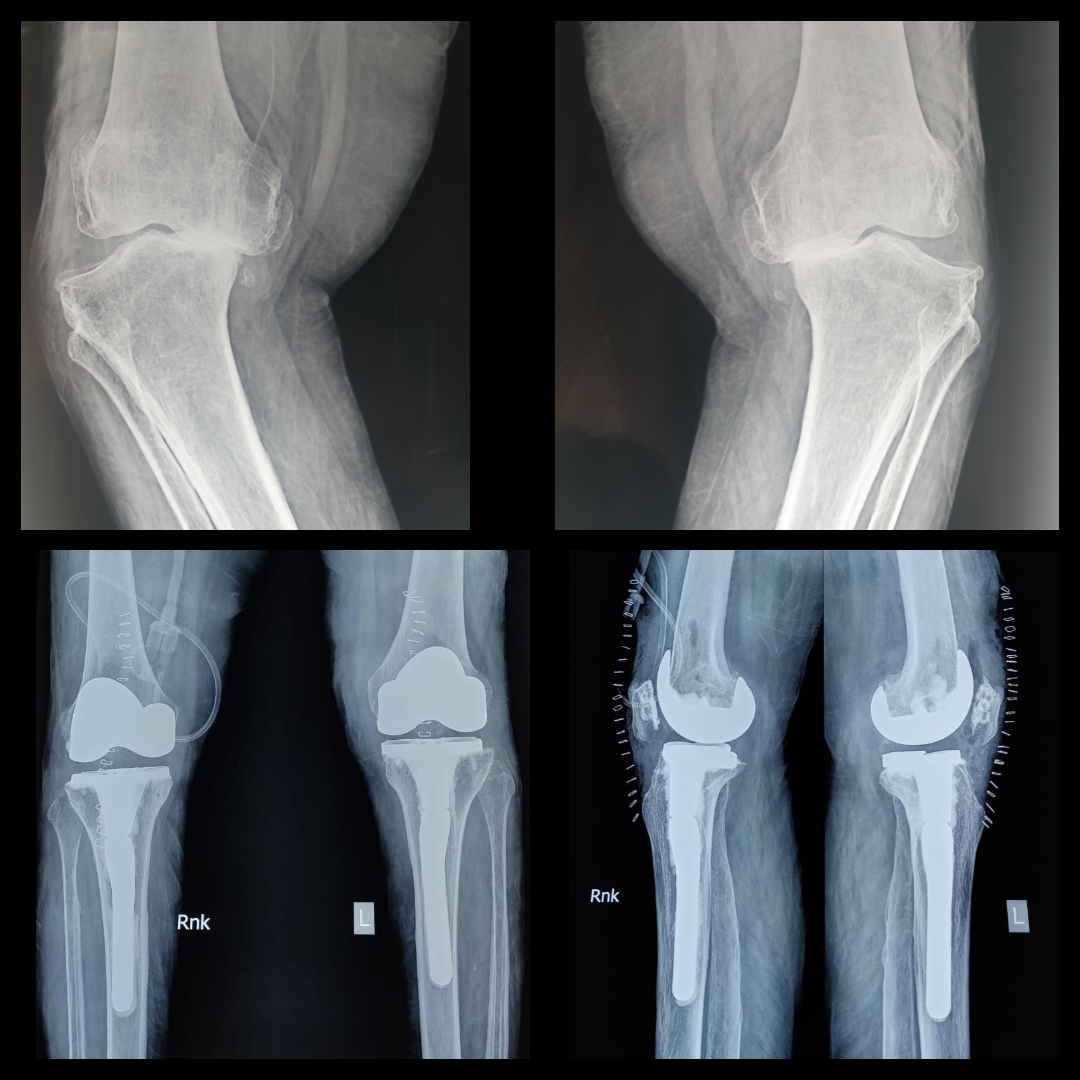

Read MoreHistory: 70-yr-old lady was unable to walk because of severe deformities. Case: This lady was operated by Dr. Amyn Rajani few days back. A long stem in the tibia is very important in such cases to prevent periprosthetic fracture. Due…